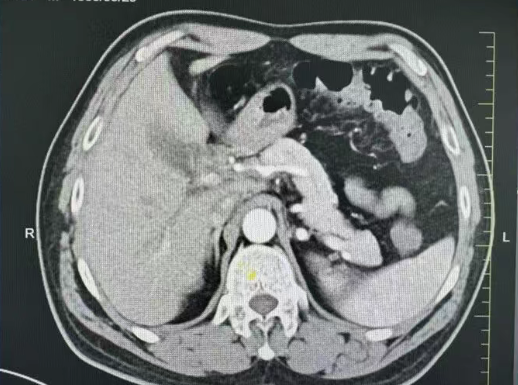

*肿瘤包绕肝动脉

在详细查阅张大爷的病历、化疗记录及影像学资料后,医院肿瘤多学科会诊(MDT)中心立即组织专家团队进行联合评估。影像资料清晰显示了肿瘤的位置、大小及其与周围血管的关系;肿瘤科专家分析了当前化疗方案的疗效与副作用;麻醉科主任评估了心肺功能及麻醉耐受能力;外科团队则重点讨论了粘连分离策略。经综合评估,明确肿瘤已达到R0切除的条件。为使手术方案更加完善,医院特邀北京知名专家前来为张大爷主刀,张大爷从未想到,在吉林也能接受到北京知名专家的诊疗服务。